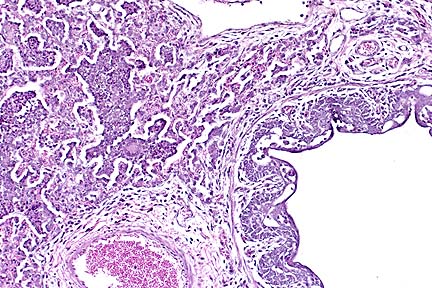

Bronchointerstitial pneumonia characteristic of morbillivirus infection in goat infected with peste des petits ruminants virus. (HE, 100X, 49K)

Histologically, PPR is characterized by necrosis of oral and intestinal epithelium and a generalized lympholysis. The pneumonia which occurs with PPR, like that associated with canine distemper or measles, is "bronchointerstitial", with disorganization of bronchiolar epithelium, and hyperplasia of type II alveolar cells. Although multinucleate syncytial cells may be see in many organs, they are most numerous in lung. Eosinophilic viral inclusion bodies may be either nuclear or cytoplasmic and are present in a variety of cell types.

AFIP Diagnosis: Lung: Pneumonia, bronchointerstitial, subacute, diffuse, severe, with bronchiolar epithelial and type II pneumocyte hyperplasia, syncytial cells, and eosinophilic intranuclear and intracytoplasmic inclusion bodies, mixed breed goat, caprine, etiology consistent with peste des petits ruminants virus.